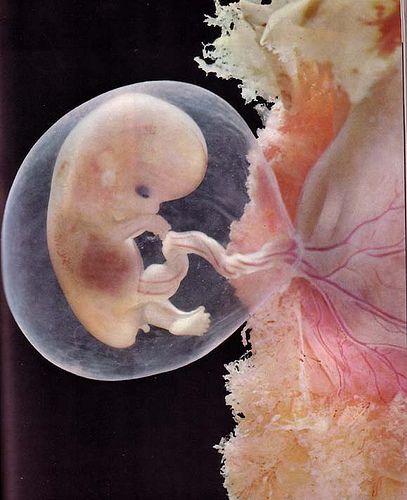

Tehát, az első héten a csírasejt tárcsa alakú, és osztódni kezd, de a végén azt beültetik a méhbe. A negyedik héten alakult a fej, a szív, a végtagok, a vérkeringés jön létre. Bár az embrió még apró, fejlődik az agy, a gerincvelő és a fej fény. Aztán a hatodik héten már vannak jelei a szem, orr, fül. Embrionális periódus véget ér 11 hét. Úgy kezdődik, a következő lépés a fejlődés.

Sok tudós javasolom, a humán embrió egy 12 hetes, ahogy alakult a kezdetektől szinte minden szerv és az is meghatározza annak a szex.

Tanulmányozásával, ami egy gyermek a méhben hetekig a fotó, a brit tudósok megállapították, hogy tudta mozgatni már 12 hetes. Egyszerűbben ez olyan kicsi, hogy az anya nem érzi ezt a mozgást. Csakúgy, mint az elején a második trimeszterben a magzat képes arra, szopás mozgásokat. Úgy néz ki, mint egy férfi: szemek várjuk, csontváz kosteneet megjelenik a zsír a bőr alatt. A gyermek agya fokozatosan alakul ki, alkotó apró nogotochki kialakítva a hangszálak. Van még egy arckifejezés! Vesék már működik.